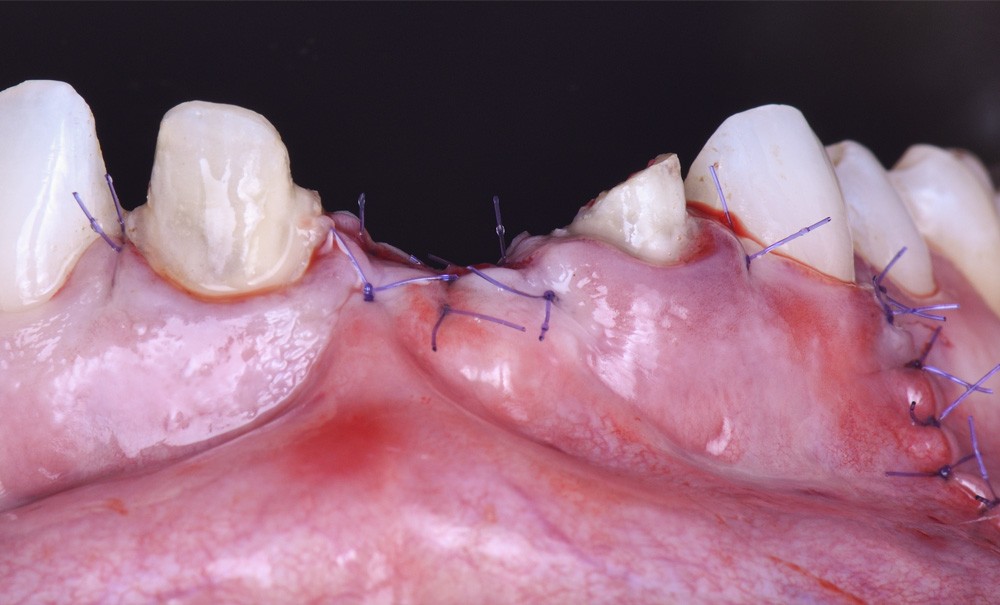

L’avulsion d’une dent est une procédure délicate et invasive ayant pour conséquence la rupture vasculaire et ligamentaire du desmodonte [1]. L’os alvéolaire étant un tissu vital, dento-dépendant, réactif et soumis à une activité métabolique complexe, il subit des remaniements constants par le biais du jeu des ostéoblastes/ostéoclastes. Que ce soit en site antérieur ou postérieur, la résorption alvéolaire postextractionnelle est inévitable, progressive dans le temps, un fait démontré dans la littérature [2]. Cette résorption affecte le volume osseux péri-implantaire, garant de la réussite des traitements. De nombreuses techniques chirurgicales permettent de conserver et d’augmenter ce volume. Parmi les greffes autogènes, l’expansion, la distraction ou encore les greffes de sinus, la régénération osseuse guidée (ROG) apparaît comme la technique la plus décrite dans la littérature, avec un taux de succès élevé. Introduite notamment par Dahlin et al. en 1988 [3], son principe majeur d’exclusion cellulaire par l’utilisation de membrane fut repris par Herman et al. en 1990 [4]. Ils démocratisaient l’utilisation de la régénération osseuse guidée concomitante à l’implantation simultanée. De nos jours, la technique de ROG doit son succès majeur aux travaux d’Istvan Urban et de son équipe [5] qui, en améliorant la technique, ont optimisé son indication en chirurgie préimplantaire d’augmentation verticale et horizontale.

Forte d’une pérennité de plus de trente ans, la technique fait l’objet d’une littérature abondante que nous recenserons, analyserons et exposerons. Les perspectives d’évolution tant par les matériaux que par les nouvelles techniques chirurgicales seront abordées. Puis, à l’aide de cas cliniques, nous détaillerons la technique en implantation précoce.